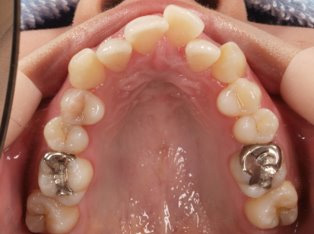

治療前

治療終了前